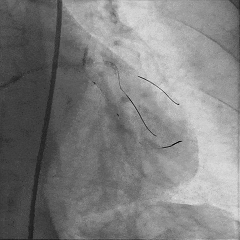

尝试通过RCA-圆锥支侧枝逆向开通LAD :

微导管辅助下,用SUOH03导丝尝试送入侧枝

经微导管TIP injection可见侧枝重度迂曲

侧枝重度迂曲,反复尝试未能通过

对角支送入IVUS导管,在IVUS实时指引下用尝试穿刺闭塞段

导丝未能进入闭塞段,导丝进入间隔支

逆向造影指引下继续尝试穿刺闭塞段

导丝远端与逆向造影不重叠,未在血管真腔

反复调整导丝最终进入D2#,可见导丝远端与D2侧枝重叠,证明远端位于真腔

微导管交换工作导丝至D2#远端

双腔微导管辅助下,导丝在逆向造影指引下成功通过LAD闭塞段,逆向造影显示导丝走行于LAD真腔内